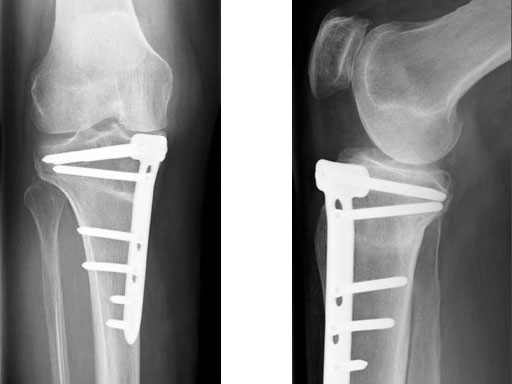

The existing TomoFix medial high tibia (TomoFix MHT) for openwedge osteotomies has been redesigned for better soft-tissue protection and to minimize rotation during compression.

The precontoured plate now has a chamfer at the proximal part and rounded edges at the lateral rims of the plate. A MIPO tapered end at the distal end was added to have a smoother pass to the bone. The two upper LCP holes in the distal part were slightly repositioned in line with the axis of the plate to eliminate the rotation of the plate during compression with cortex screws because of the former asymmetrical alignment of the holes. The two most distal LCP holes were changed to isolated LCP holes to hinder the use of cortex screws.

The KNEG is working on further improvements to the implants. The TomoFix Medial Tibia Shaft will get slimmer, as the combination holes on the shaft will be exchanged against simple locking holes. The edges will be rounded to help avoid morbidity from the implant. These design modifications have been tested biomechanically and no disadvantages have been recognized against the present plate design. In addition, a smaller version of the plate is presently in preparation, mainly adapted to the specific anatomy of the Asian proximal tibia. Development of this plate is strongly supported by the input of our Japanese friends R Takeuchi and T Sawaguchi. First prototypes will undergo biomechanical testing in the near future.